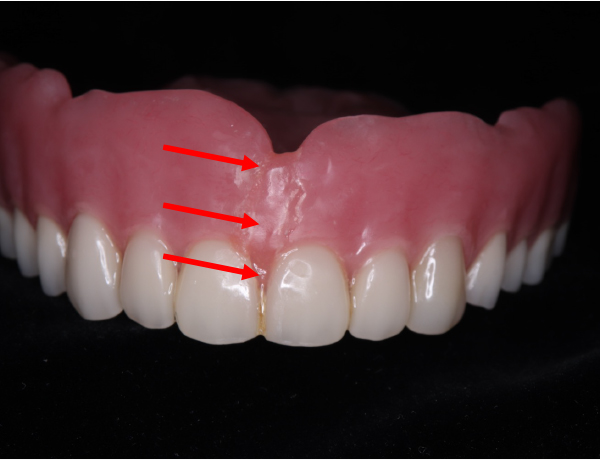

上の入れ歯にヒビが入っている

青い矢印で示している部分に、以前からヒビが入っている状態が確認できます。

このヒビは、前歯が脱落した部分まで一直線に伸びており、入れ歯全体に大きな負担がかかっていたことが分かります。

また、上の入れ歯を詳しく観察すると、歯の並びが左右でアンバランスになっているように見えます。

このような歯の配置のズレがあると、噛み合わせに偏りが生じ、特定の部位に過剰な力が加わることで、入れ歯が割れてしまった可能性が考えられます。

保険の入れ歯をセットしてから、3ヶ月後入れ歯にヒビが入ったと患者さんから連絡が入りました。どれどれと見てみると、上あごの入れ歯にヒビが入っています。正面から見てもちょうど真ん中にヒビが入っています。

咬合面観

正面観